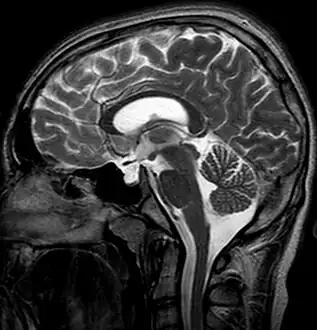

| MRI of Empty Sella | |

Empty sella- MRI Scan of the brain, sagittal T2-weighted

Empty sella in MRI